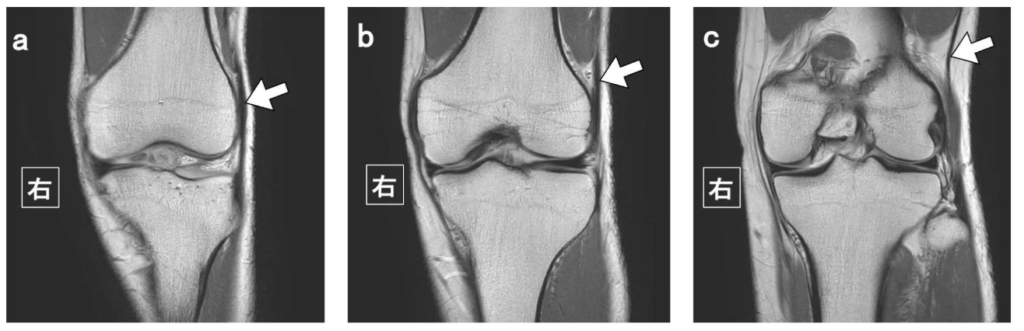

問題 31 左膝のT2強調冠状断像を示す。矢印が示す解剖構造はどれか。

1. 鵞足

2. 腸脛靭帯

3. 外側広筋

4. 外側側副靱帯

5. 内側側副靱帯

問題 37 頸椎のMRI矢状断像(a:T2強調像、b:T1強調像、c:0(ゼロ)TE白黒反転像)を示す。矢印が示す病変として最も疑われるのはどれか。

1. 多発性硬化症

2. 多発性骨転移

3. 椎間板ヘルニア

4. 黄色靱帯骨化症

5. 後縦靱帯骨化症